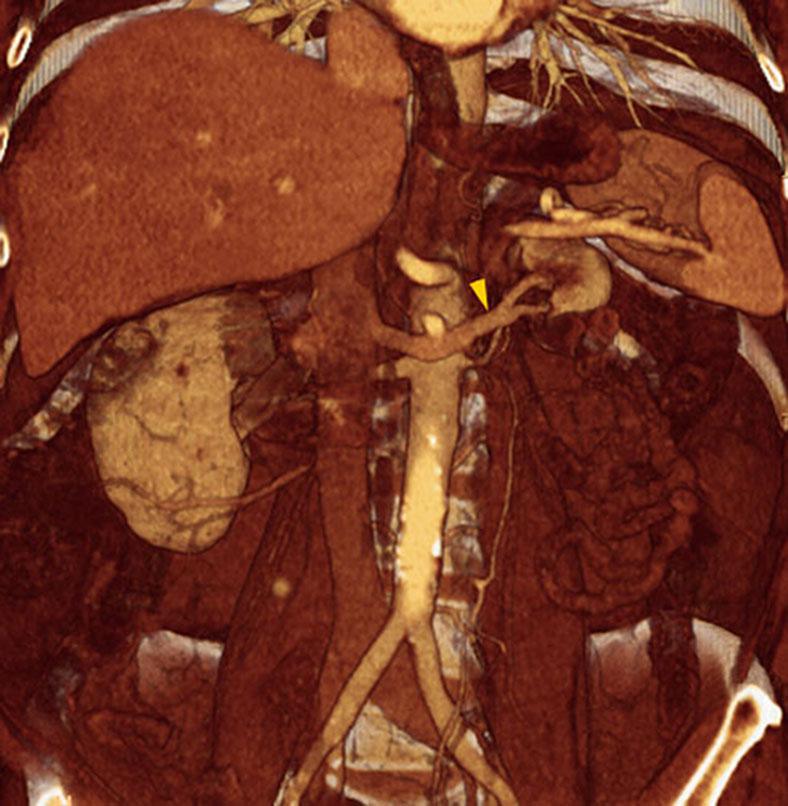

Riñón único pélvico